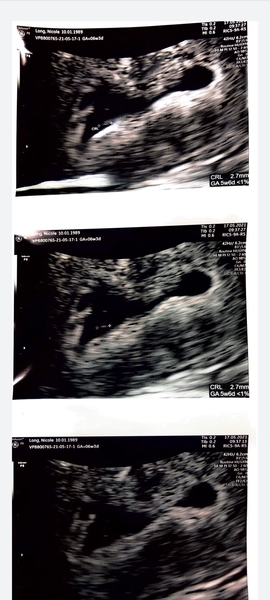

Hi ladies!!

My scan went really well!! Bean in measuring 7+1 and i'm 7w today! So perfect. Had a strong heartbeat (we only saw it) and my cervix is nice and closed and all looks perfect.

So we are very happy and excited

Here he is! Grin